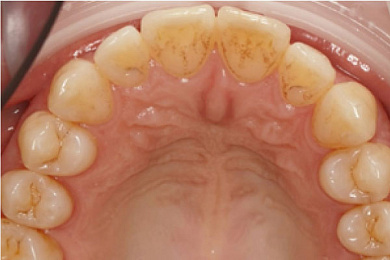

Нередко даже при хорошей гигиене полости рта на зубах образуется мягкий налёт, который в дальнейшем покрывает весь зуб и начинает отвердевать, постепенно превращаясь в зубной камень, который может провоцировать многие заболевания зубного ряда некариозного характера.

- При помощи специального ультразвукового скайлера бережно удаляются крупные зубные камни: это происходит при помощи создаваемых скайлером колебаний, который буквально «сбивает» каждый камень.

- Затем проводится удаление мягкого налёта аэрозольным методом: зубы обрабатываются составом: вода с мельчайшими абразивными частицами бережно очищает поверхность зубов от налёта. Благодаря этой процедуре зубы становятся светлее сразу на 1-2 тона.